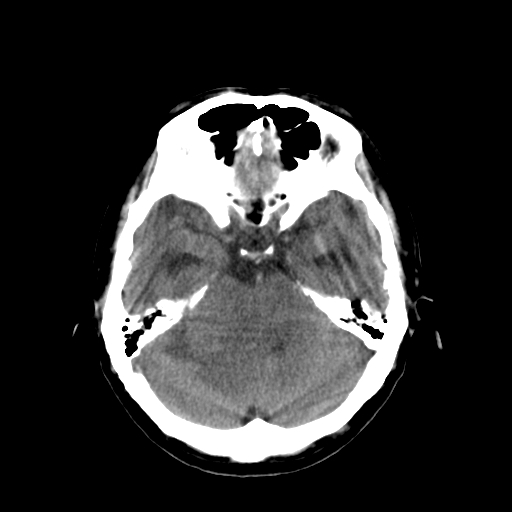

男,34岁,头痛数天。请大家看看是否有占位.

脑干、右侧桥臂及右侧小脑半球可见等低混杂密度影,环池部分闭塞,小脑上池及第四脑室受压移位、闭塞,考虑占位性病变可能性大,胶质瘤?室管膜瘤?不除外脑神经如听神经瘤及梗塞等,建议上传骨窗

右侧小脑半球占位压迫四脑室并幕上脑积水征像;建议增强或mr检查

右侧小脑半球病变压迫四脑室并幂上积水征象,考虑占位.

脑干、右侧桥臂及右侧小脑半球可见等低混杂密度影。轻度脑积水。考虑右侧桥臂区域占位性病变。建议mri检查。

右侧桥小脑区见等混杂密度占位影,病变境界不清,环池部分闭塞,四脑室受压左移,建议上传增强或mr检查片...